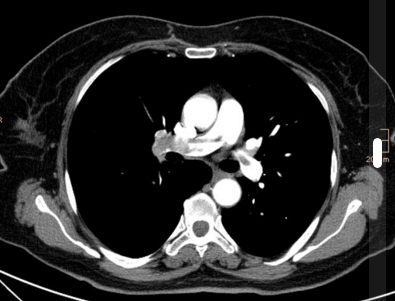

CTPA (spiral CT in arterial phase with a contrast bolus 4ml/sec) is NICE recommended. It has good sensitivity and specificity. It is available 24/7 in all acute hospitals (unlike other possible imaging modalities). Multiplanar reconstructions are very helpful for spotting more subtle PEs. RV > LV diameter on CT is a sign of R heart strain, which SpRs should be able to recognise to aid risk assessment. Image quality is degraded by high BMI (grainy images) and poor contrast (not in phase well so harder to see defect) – 250-300 Hounsfield needed for good diagnosis.

Pulmonary embolism. Case courtesy of Dr Stefan Ludwig, Radiopaedia.org. From the case rID: 13894